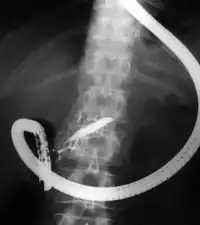

Endoscopic retrograde cholangiopancreatography (ERCP) is a technique that combines the use of endoscopy and fluoroscopy to diagnose and treat certain problems of the biliary or pancreatic ductal systems. It is primarily performed by highly skilled and specialty trained gastroenterologists. Through the endoscope, the physician can see the inside of the stomach and duodenum, and inject a contrast medium into the ducts in the biliary tree and pancreas so they can be seen on radiographs.

ERCP is used primarily to diagnose and treat conditions of the bile ducts and main pancreatic duct,[1] including gallstones, inflammatory strictures (scars), leaks (from trauma and surgery), and cancer. ERCP can be performed for diagnostic and therapeutic reasons, although the development of safer and relatively non-invasive investigations such as magnetic resonance cholangiopancreatography (MRCP) and endoscopic ultrasound has meant that ERCP is now rarely performed without therapeutic intent.[2]

The patient is sedated or anaesthetized. Then a flexible camera (endoscope) is inserted through the mouth, down the esophagus, into the stomach, through the pylorus into the duodenum where the ampulla of Vater (the union of the common bile duct and pancreatic duct) exists. The sphincter of Oddi is a muscular valve that controls the opening to the ampulla. The region can be directly visualized with the endoscopic camera while various procedures are performed. A plastic catheter or cannula is inserted through the ampulla, and radiocontrast is injected into the bile ducts and/or pancreatic duct. Fluoroscopy is used to look for blockages, or other lesions such as stones.[8][9]

When needed, the sphincters of the ampulla and bile ducts can be enlarged by a cut (sphincterotomy) with an electrified wire called a sphincterotome for access into either so that gallstones may be removed or other therapy performed.[10]

Other procedures associated with ERCP include the trawling of the common bile duct with a basket or balloon to remove gallstones and the insertion of a plastic stent to assist the drainage of bile.[11] Also, the pancreatic duct can be cannulated and stents be inserted.